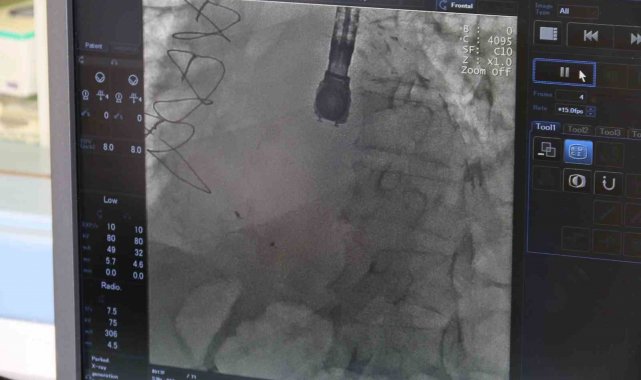

Kardiyoloji Uzmanı Dr. Bektaş Murat, kronik rahatsızlıkları olan ve bunların ameliyatı zorlaştıracağını öngörerek ameliyat kararı aldı. Anjiyografi adlı yöntemle kasıktan girerek kalpteki deliği uzun ve meşakkatli süren ameliyat sonrası kalpteki delik kapatılmış oldu. Ameliyat sonrası durumu takip edilen hasta, taburcu edildi. Böylelikle 68 yaşındaki İbrahim Serdar Şenat, bu operasyonu geçirip de yaşayan 9 hastadan biri oldu.

Operasyonla alakalı konuşan Eskişehir Şehir Hastanesi'nde görevli Kardiyoloji Uzmanı Dr. Bektaş Murat, "Hastamız polikliniğimize nefes darlığı ve kalp yetersizliği semptomuyla başvurdu. Ancak hastamızın hikâyesini aldığımızda yaklaşık 20 gün önce başka bir merkezde kalp krizi geçirdiğini ve anjiyografiyle tedavi edildiğini öğrendik. Muayene sırasında kalp kriziyle beraber ortaya çıkan, kalp karıncıklarının duvarında VSD dediğimiz bir kalp deliğinin meydana geldiğini öğrendik. Bu gerçekten çok ciddi bir durum. Kalp krizine bağlı olarak çok nadir bir şekilde gerçekleşiyor; ancak nadir gelişse de ölümcül olabilen bir hastalık. Dolayısıyla bu gelişen komplikasyonu hızlı bir şekilde tedavi etmemiz gerekiyordu. Onun için hastamızı yoğun bakıma yatırdık ve ileri tetkiklerini yaptık. İleri tetkikler sonucunda 'Ventriküler Septal Defekt' (VSD) dediğimiz bu hastalığın, kalp krizine bağlı olarak geliştiğini ve kalbin duvarında delik şeklinde olduğunu tespit ettik. Hastanemizdeki kalp ekibiyle de hemen bir istişare yaparak tedavi yöntemi üzerinde çalıştık. Normalde bu hastalığın tedavisi için ilk aşamada cerrahi müdahale öneriliyor ancak hastamızın altta yatan ciddi hastalıklarının olması nedeniyle cerrahi işlemin çok yüksek riskli olduğu kararına varıldı. Sonrasında bu işlemi girişimsel olarak yapmamız için karar verildi. İlk önce hastamızın acil durumunu tedavi edip sonrasında da ekibimizle beraber kasıktan girme operasyonu yaparak, kalpteki deliği de kapatmış olduk" dedi.